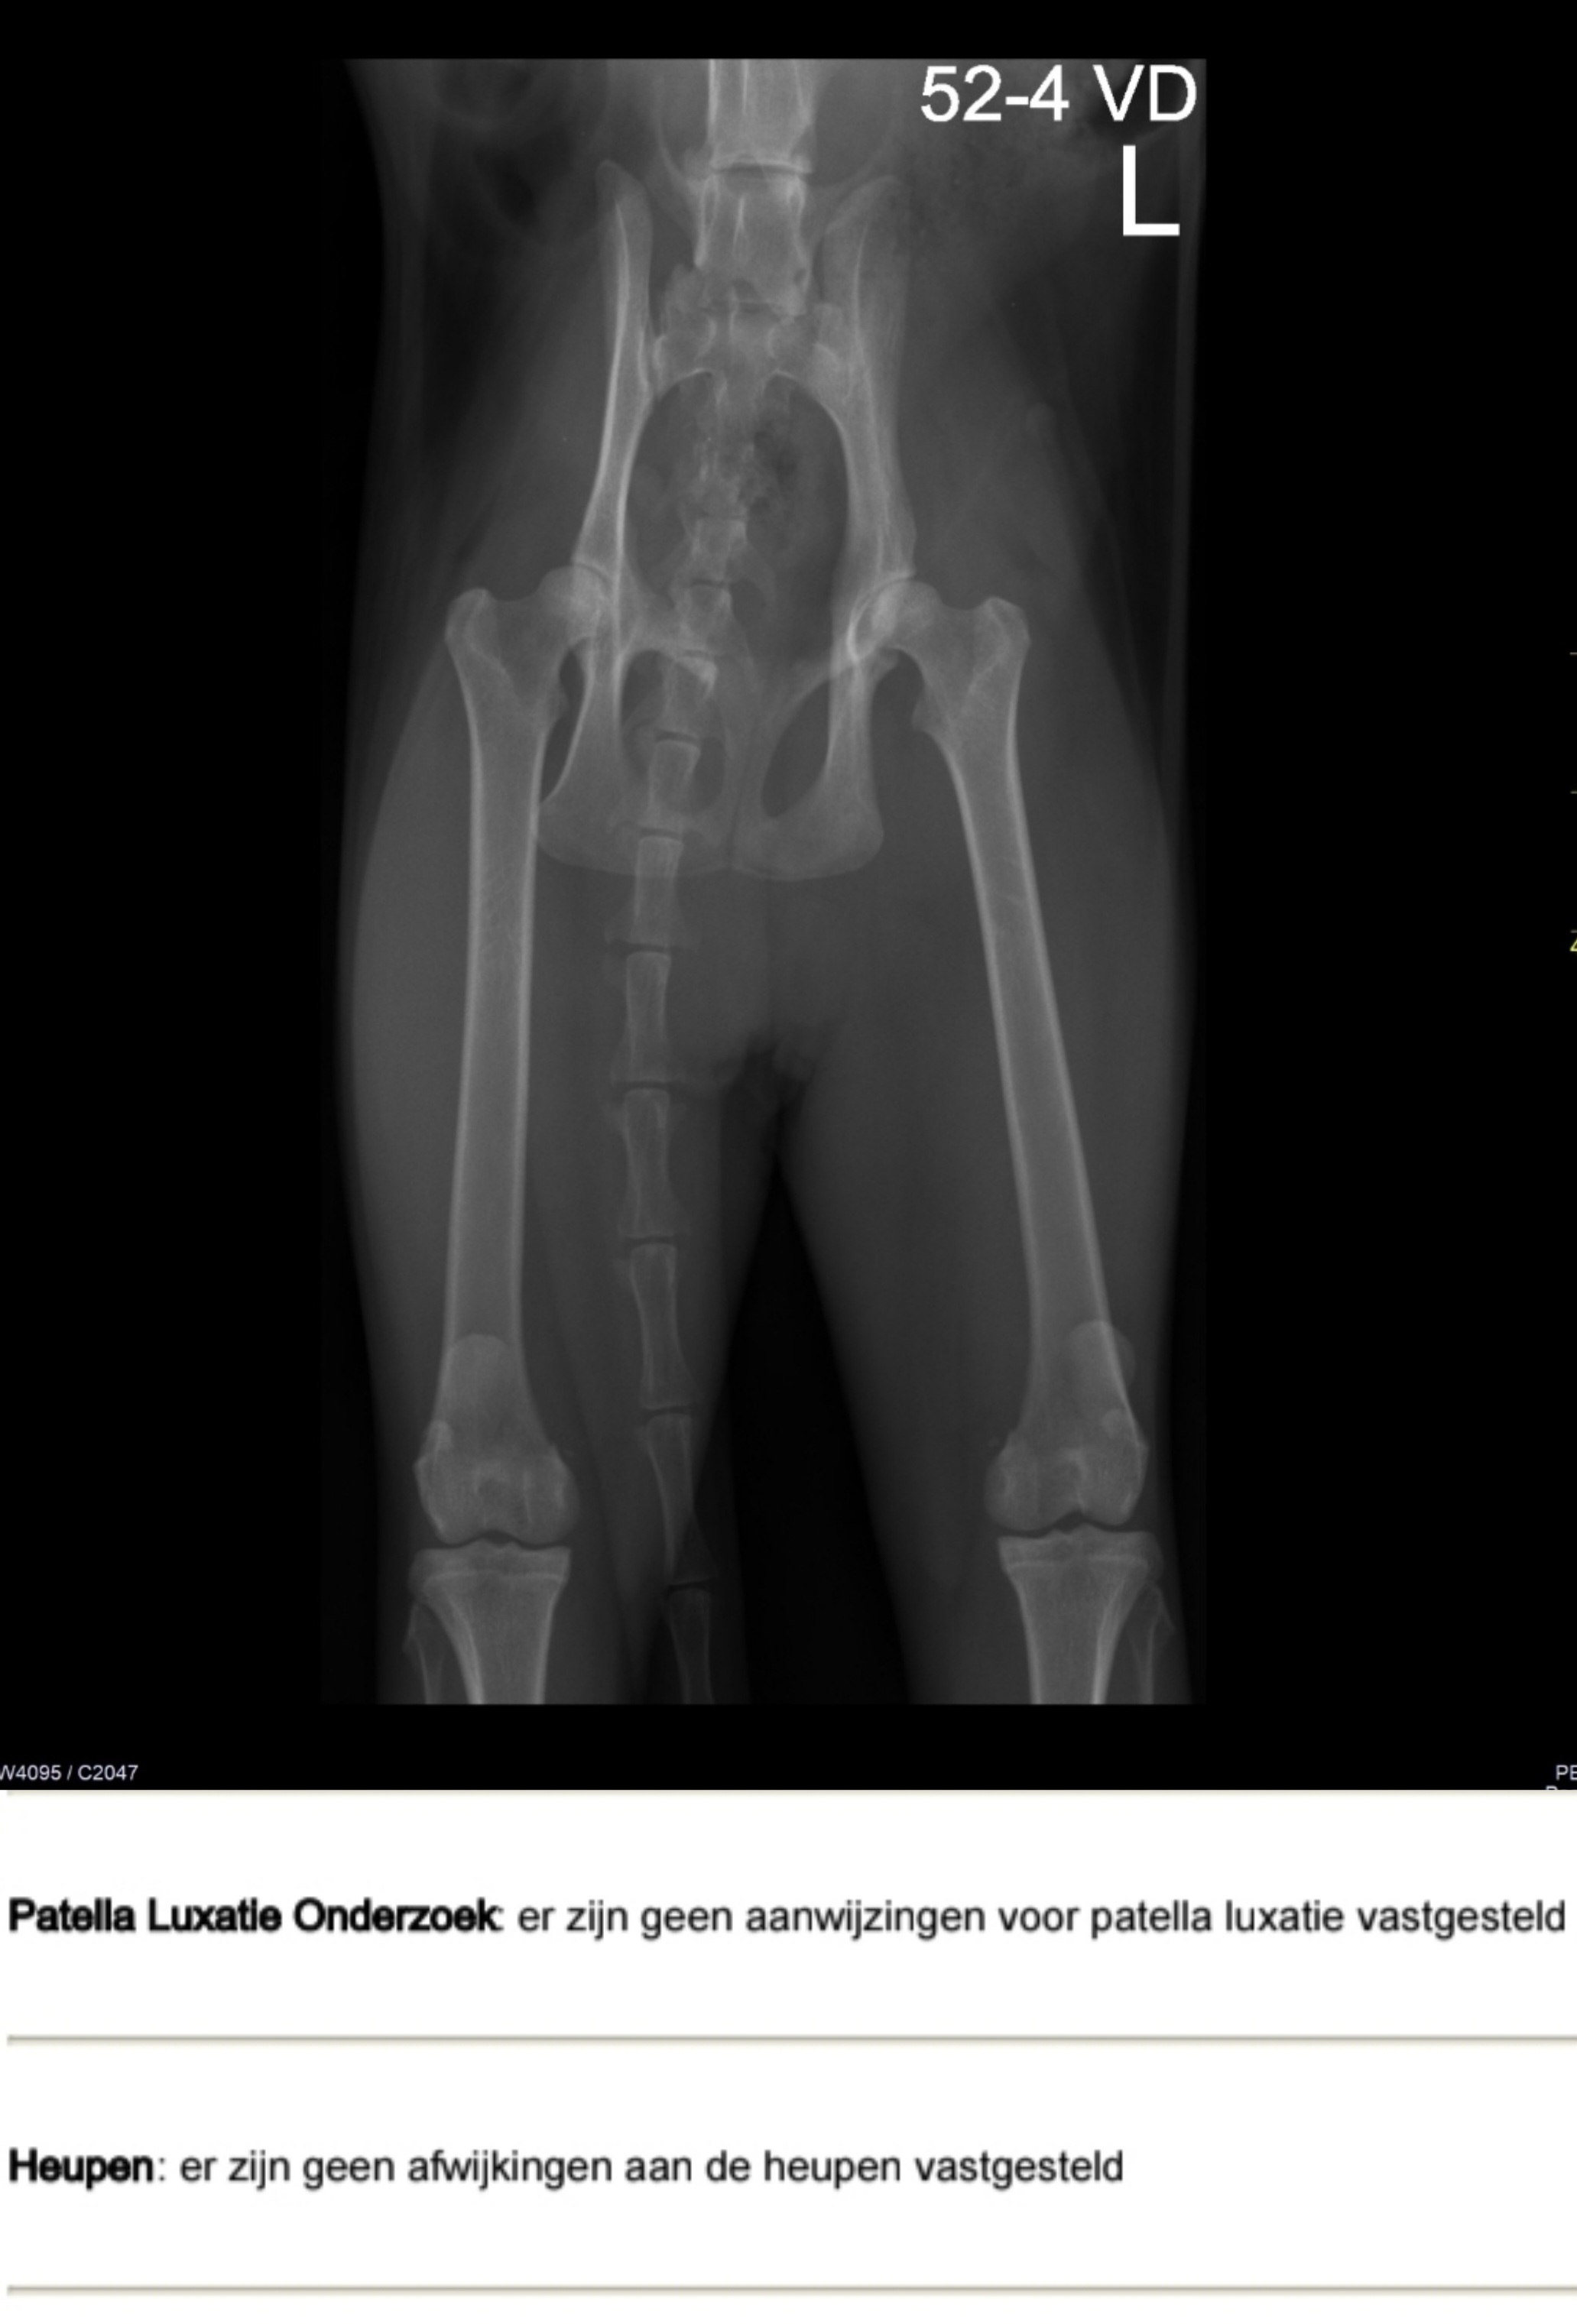

Heupen

Afbeelding – 400,9 KB

41 downloads

Download